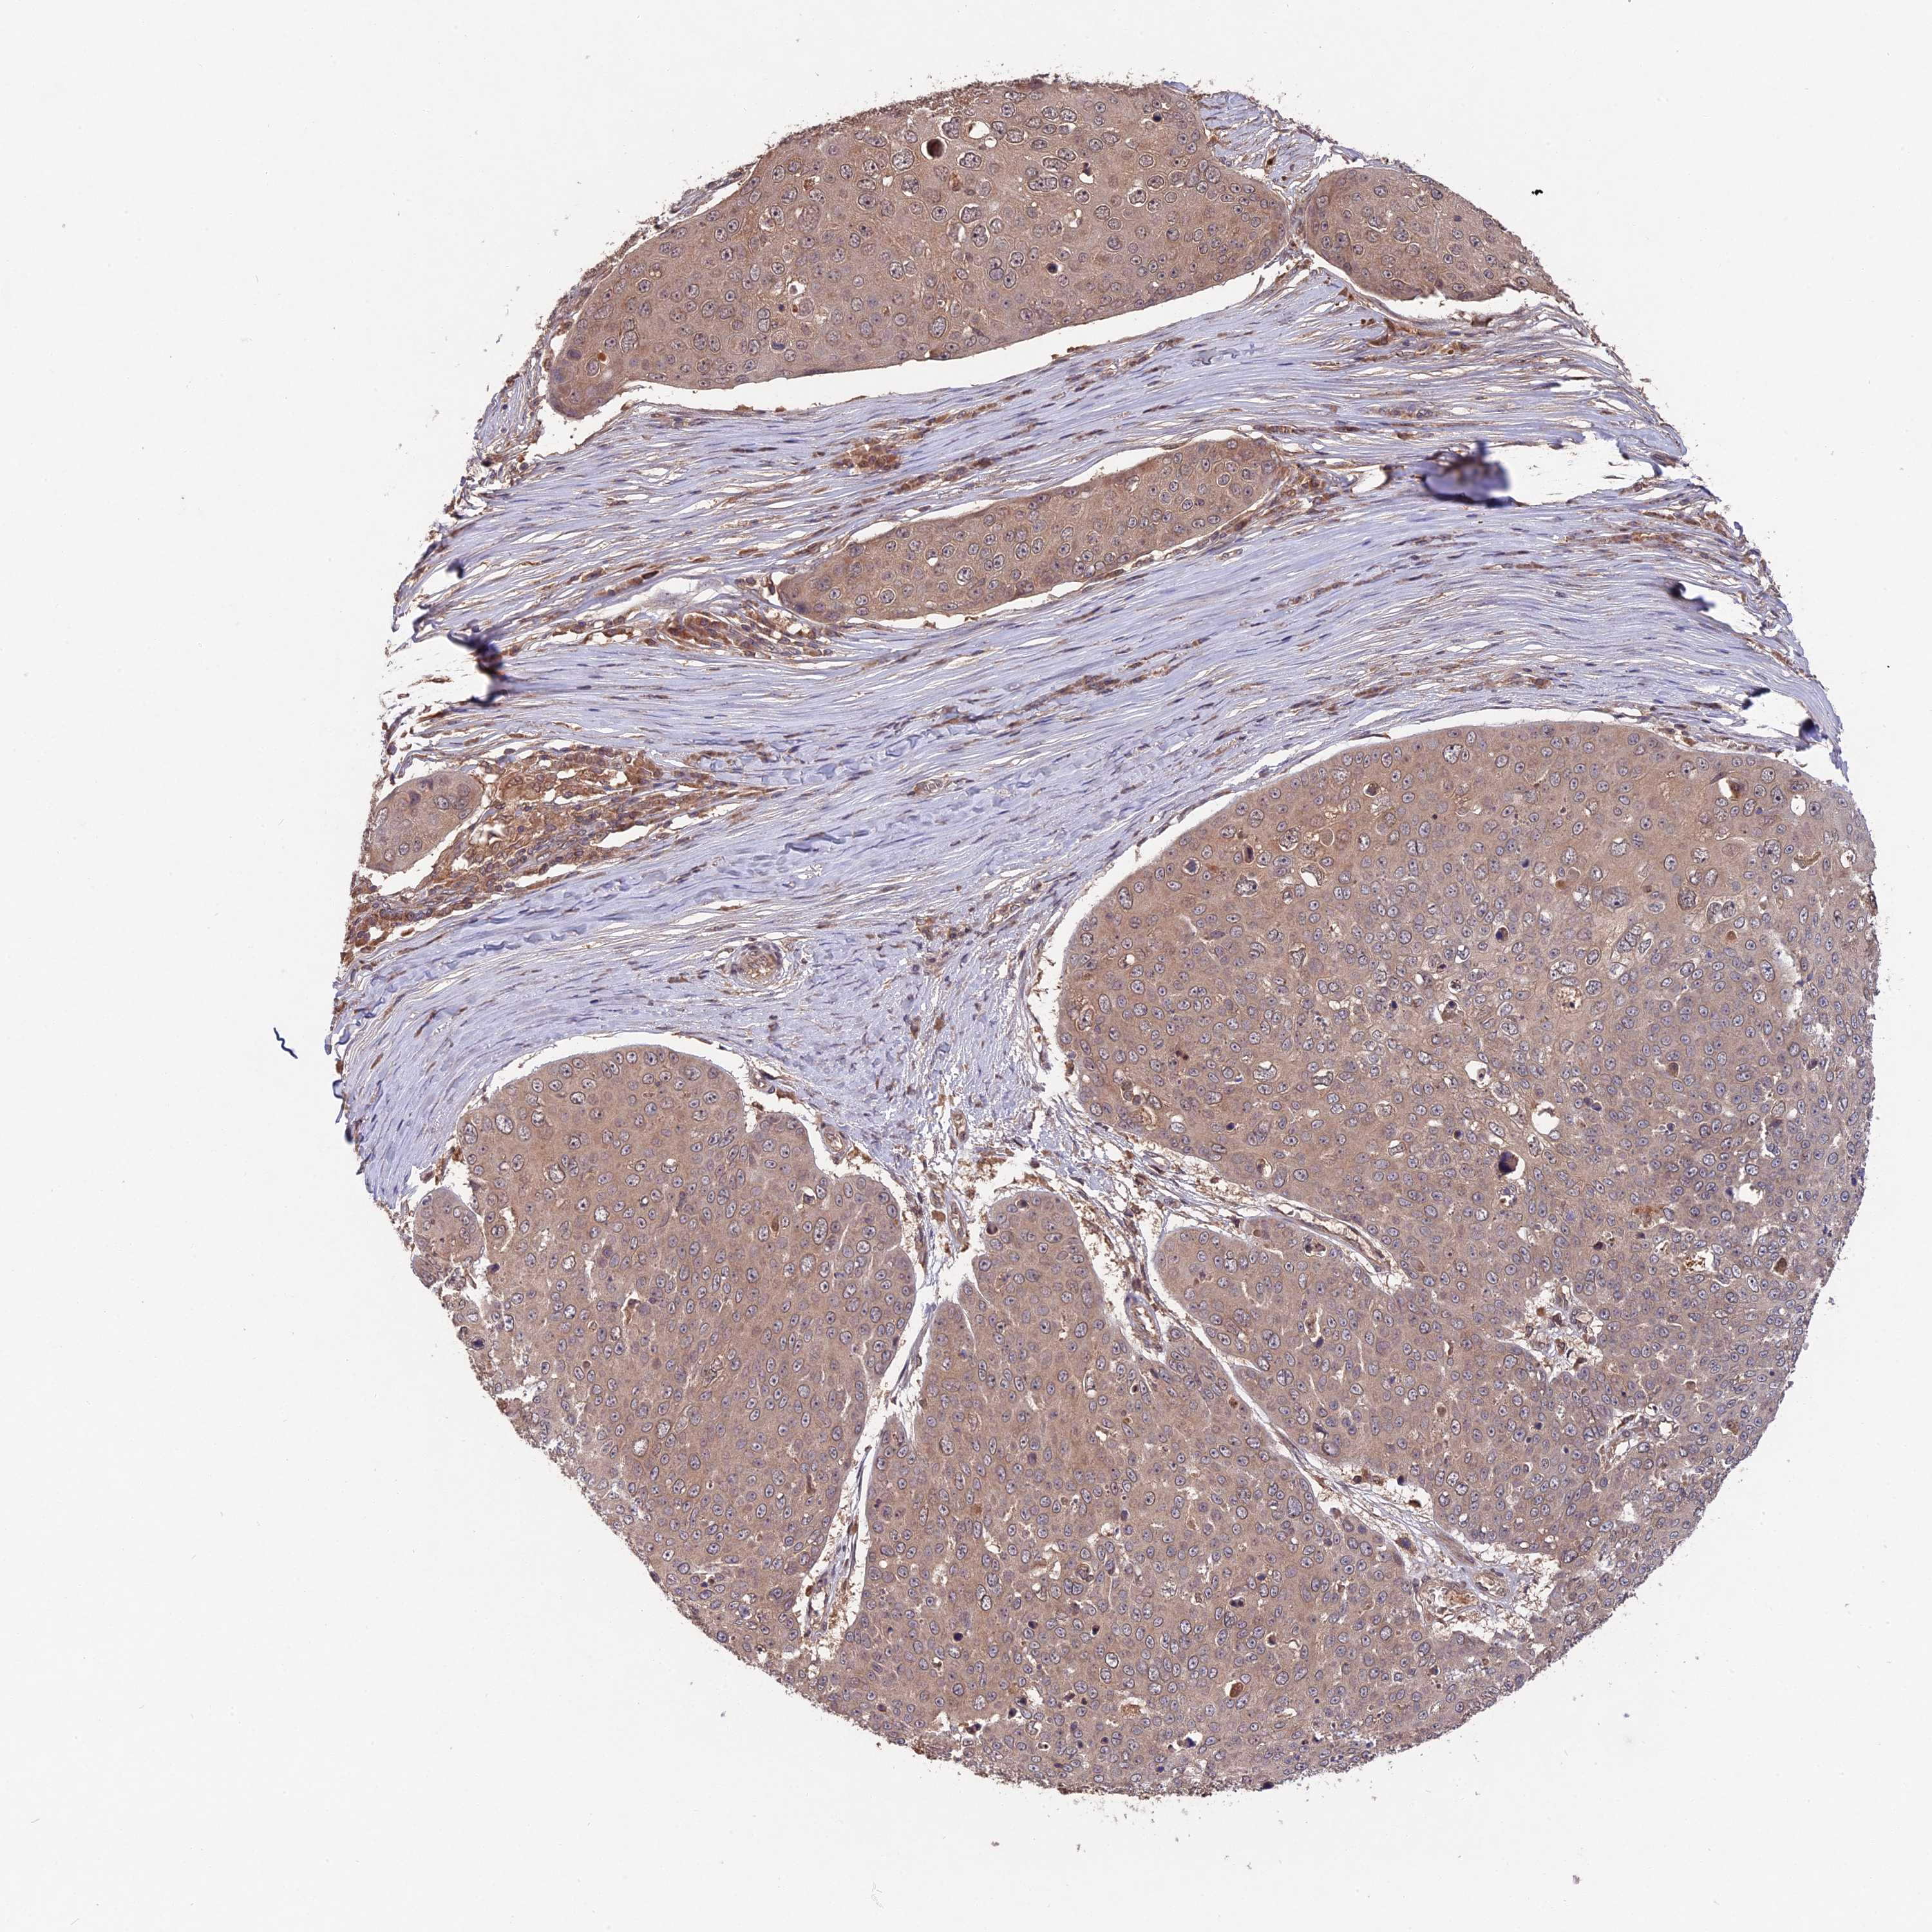

SKIN CANCER - Protein expressioni

A mouse-over function shows sample information and annotation data. Click on an image to view it in a full screen mode. Samples can be filtered based on level of antibody staining by selecting one or several of the following categories: high, medium, low and not detected. The assay and annotation is described here.

Antibody stainingi

Antibody staining in the annotated cell types in the current human tissue is reported as not detected, low, medium, or high, based on conventional immunohistochemistry profiling in selected tissues. This score is based on the combination of the staining intensity and fraction of stained cells.

Each image is clickable and will lead to virtual microscopy that enables deeper exploration of all samples and also displays staining intensity scores, fraction scores and subcellular localization as well as patient and tissue information for each sample.

Antibody HPA042708

Antibody HPA043505

Basal cell carcinoma

Squamous cell carcinoma, NOS

Squamous cell carcinoma, metastatic, NOS